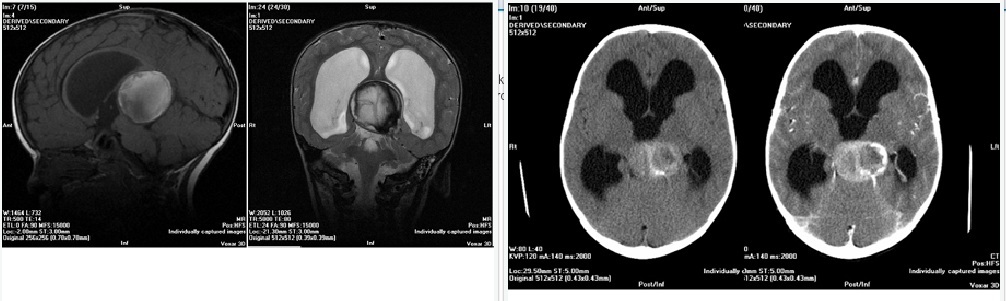

Seorang anak berusia 2,5 tahun dengan makroensefal dan gagal tumbuh kembang. Dia baru mulai bisa berjalan tetapi memiliki perkembangan bicara yang tidak sesuai dengan umur. Pada CT scan dam MRI tampak lesi pada regio pineal. Serum Beta HCG dan AFP negatif. Prosedur yang paling memungkinkan untuk dilakukan adalah

In this case, the pineal region lesion is not a tumor, but a Vein of Galen Malformation. Biopsy or attempt at open resection would be disastrous. This case emphasizes the need to carefully image, and in appropriate cases obtain angiography, for pediatric cases that may involve vascular lesions. Vein of Galen malformations present variably by age. Newborn children typically present in severe congestive heart failure due to high flow shunting through the malformation, and often macrocephaly. Older children may present first with hydrocephalus, usually with a slower flow lesion. Yasargil classified Vein of Galen Malformations in the following manner: 1: pure fistula of ACA or PCA branch to vein of galen, 2: Fistulous thalamoperforating vessels to Vein of Galen, 3: Combined lesions, and 4: Plexiform AVMs. Treatment options include endovascular techniques (both transarterial and transvenous), observation with management of hydrocephalus and rarely, open surgical techniques. Prognosis is related to age at presentation, cardiac status and presence of calcifications in the basal ganglia, as a marker of cererbral injury due to steal. In older children, non-operative management or hydrocephalus management alone can be successful. In this case, angiography showed a slow flow lesion which was seen to thrombose on follow-up studies.